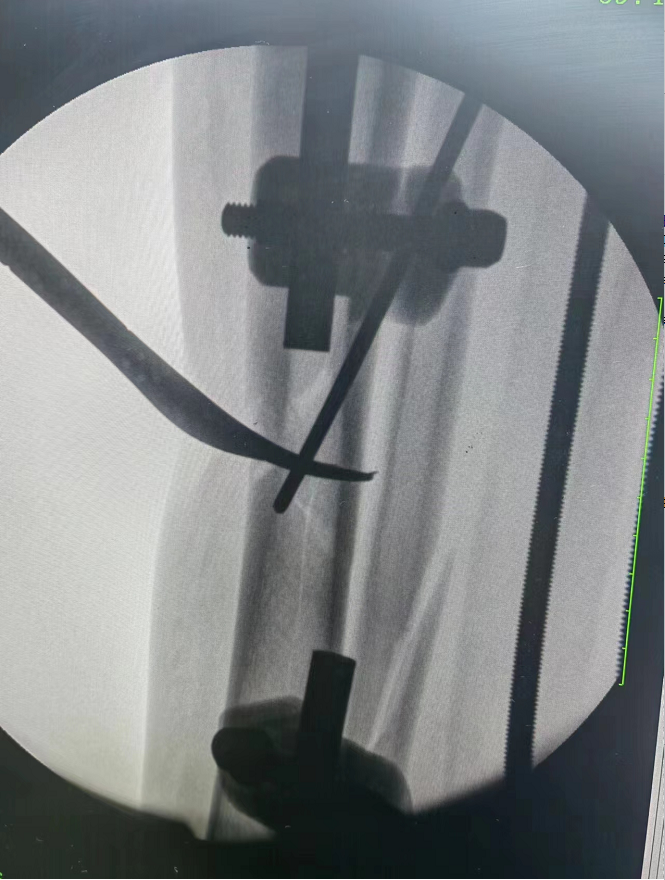

术中X片